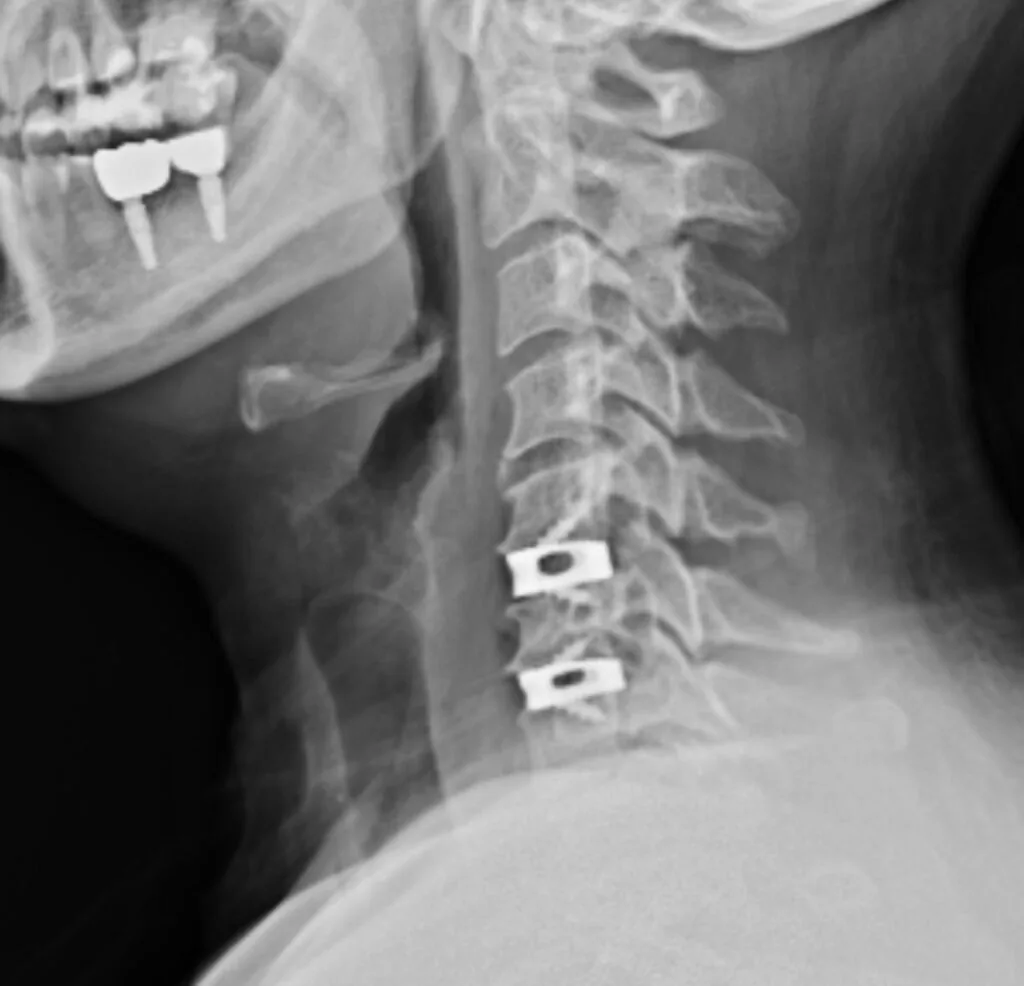

- Radiografia da coluna cervical: avalia o alinhamento vertebral e possíveis alterações degenerativas ósseas.

1. Discectomia cervical anterior com fusão (ACDF)

É a técnica mais utilizada para hérnia cervical. Realizada pela parte frontal do pescoço, o disco afetado é retirado e substituído por um espaçador (cage) que promove a fusão das vértebras. Tem alta taxa de sucesso e boa evolução.

2. Prótese de disco cervical (artroplastia)

Alternativa à fusão, a prótese preserva o movimento da coluna. Indicada para casos selecionados, especialmente em pacientes mais jovens com doença em um único nível.